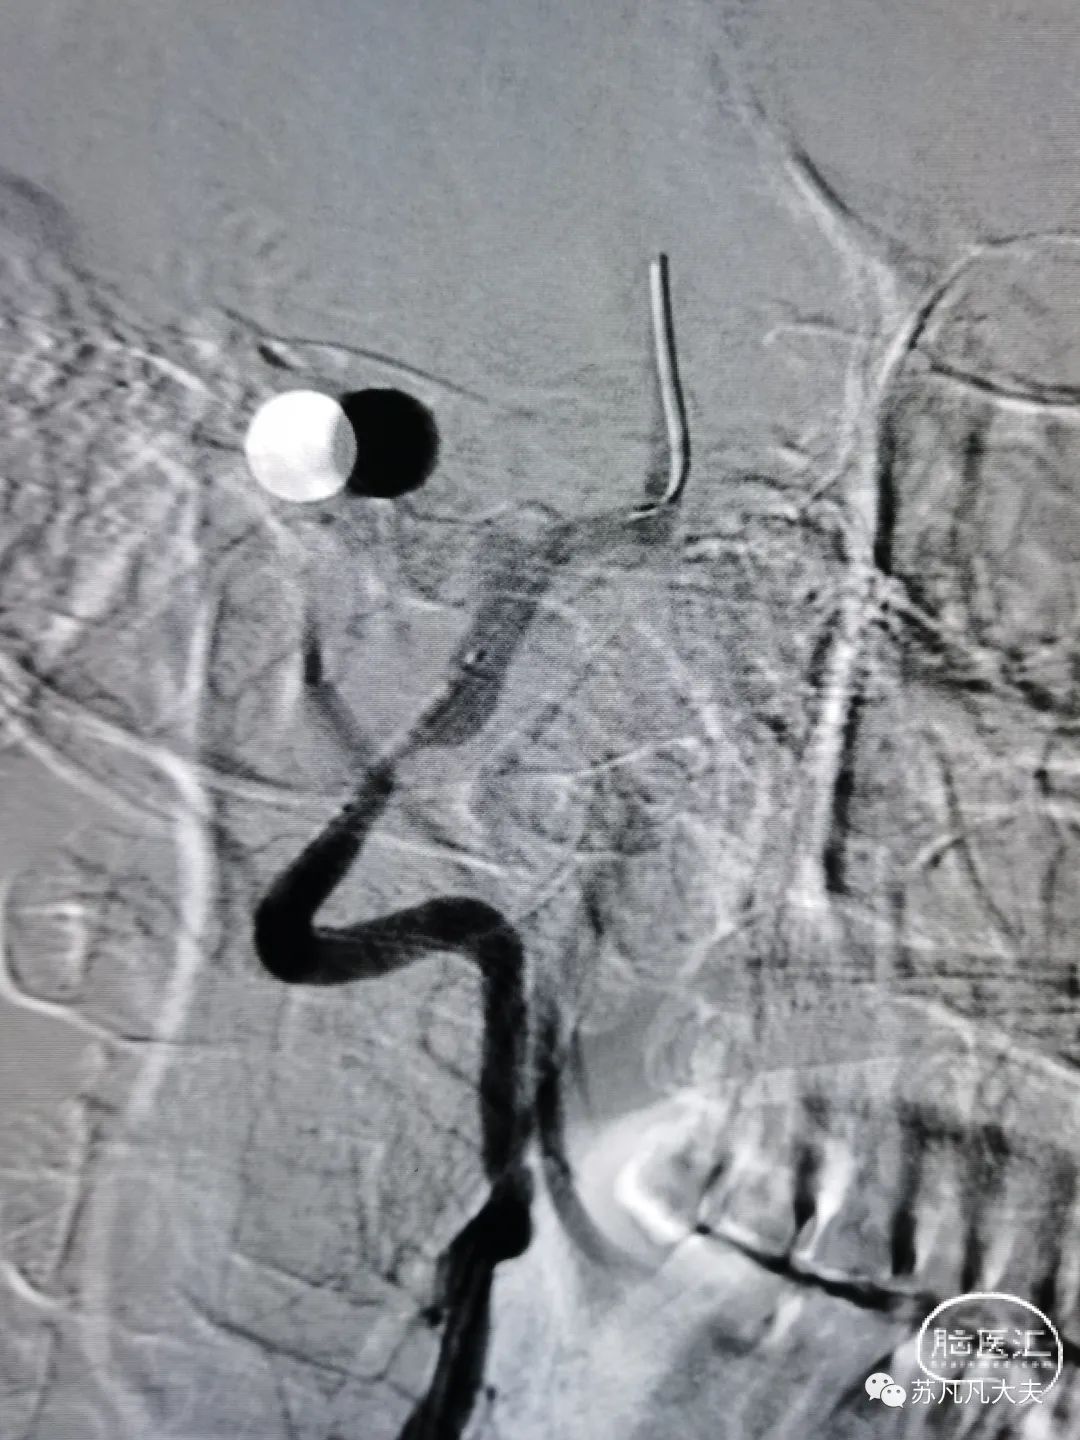

DSA示右椎发育不良,颅内段闭塞

DSA示左椎优势,V4段极重度狭窄,左侧大脑后动脉未显影